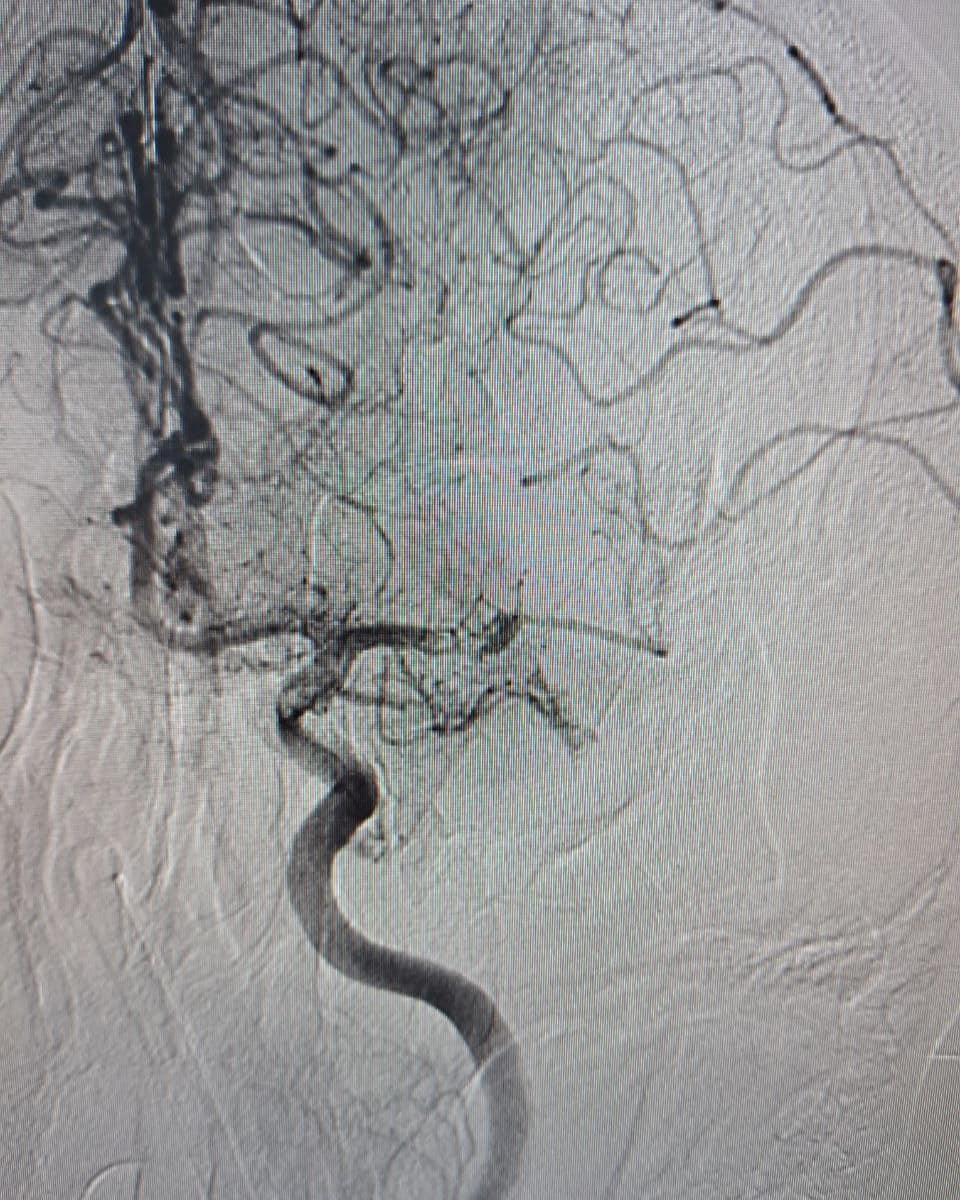

Вчергове у КНП «Нововолинська ЦМЛ» врятували пацієнта з інсультом. Хворому провели видалення тромбу з мозку мініінвазивно, через маленький прокол в паховій ділянці.

Тромбоекстракція – найсучасніший ендоваскулярний метод лікування ішемічного інсульту в гострому періоді. Він полягає у видаленні тромбу з артерій головного мозку з подальшим відновленням кровотоку та запобіганню розвитку ішемічного інсульту в даній ділянці.

Виконується дане ендоваскулярне втручання на ангіографічній системі за допомогою стента-ретрівера – спеціального циліндричного металічного пристрою, який вводиться безпосередньо в тромб, захоплює його і видаляє з закупореної судини.